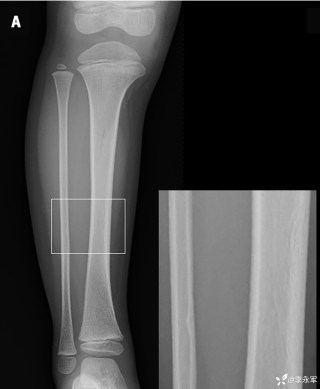

2023年10月26日,来自山东菏泽市成武县的小烨和他家人的命运被彻底改变了。这个原本阳光、可爱的小男孩在一次意外被撞击后,在医院检查出了腹腔内存在肿瘤,并在手术中被切除了包括十二指肠、胰腺、大部分胃和小肠等多个器官。此后便无法再像正常人一样吃饭、喝水,活着要靠长期静脉注射营养液。一份2024年12月由第三方机构出具的司法鉴定意见书显示,当时给小烨做手术的成武县人民医院在该医疗行为中存在过错,与小烨的损害后果之间存在因果关系,建议医疗过错在损害后果中的原因力大小为同等原因。此外,另一份由成武县卫生健康局在2025年9月28日发出的书面答复中显示,成武县人民医院存在24小时内未完成病历;手术知情